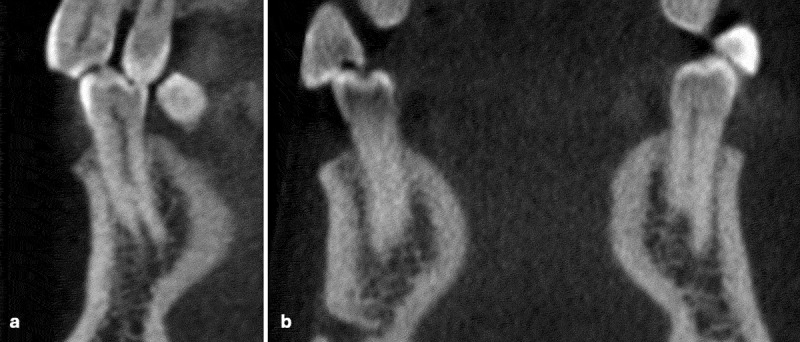

In-depth knowledge of the anatomical structure of the root canal system is fundamental for successful endodontic treatment. This research aimed to evaluate the root canal structures of lower premolars in the Saudi western demographic via Cone Beam Computed Tomography (CBCT) scans. 760 CBCT scans were reviewed, which incorporated 2747 mandibular premolar teeth. SPSS was employed for descriptive statistics and Pearson chi-square tests. The Kappa tests were executed for intra- and inter-observer consistency. The number of roots, canals, and canal configurations based on Vertucci's classification were assessed. The study further explored the prevalence, patterns, and variations of the root canal systems, considering gender-based variations and bilateral resemblance. Predominantly, mandibular premolars possessed a single root, though a minority displayed two or three roots. The occurrence of multiple canals was also on the lower side, with the type I canal pattern emerging predominantly. Gender-based distinctions were evident, as males exhibited a higher frequency of two-rooted premolars and multiple canals than females. It was noted that the anatomical differences were more in the mandibular first premolars than in the second premolars. A significant bilateral consistency was observed, with most teeth showcasing consistent root and canal numbers. This research offers essential perspectives on the diverse nature and variability of root canal anatomy within the Saudi Western cohort, facilitating better understanding and treatment planning in endodontics.

Abstract Image